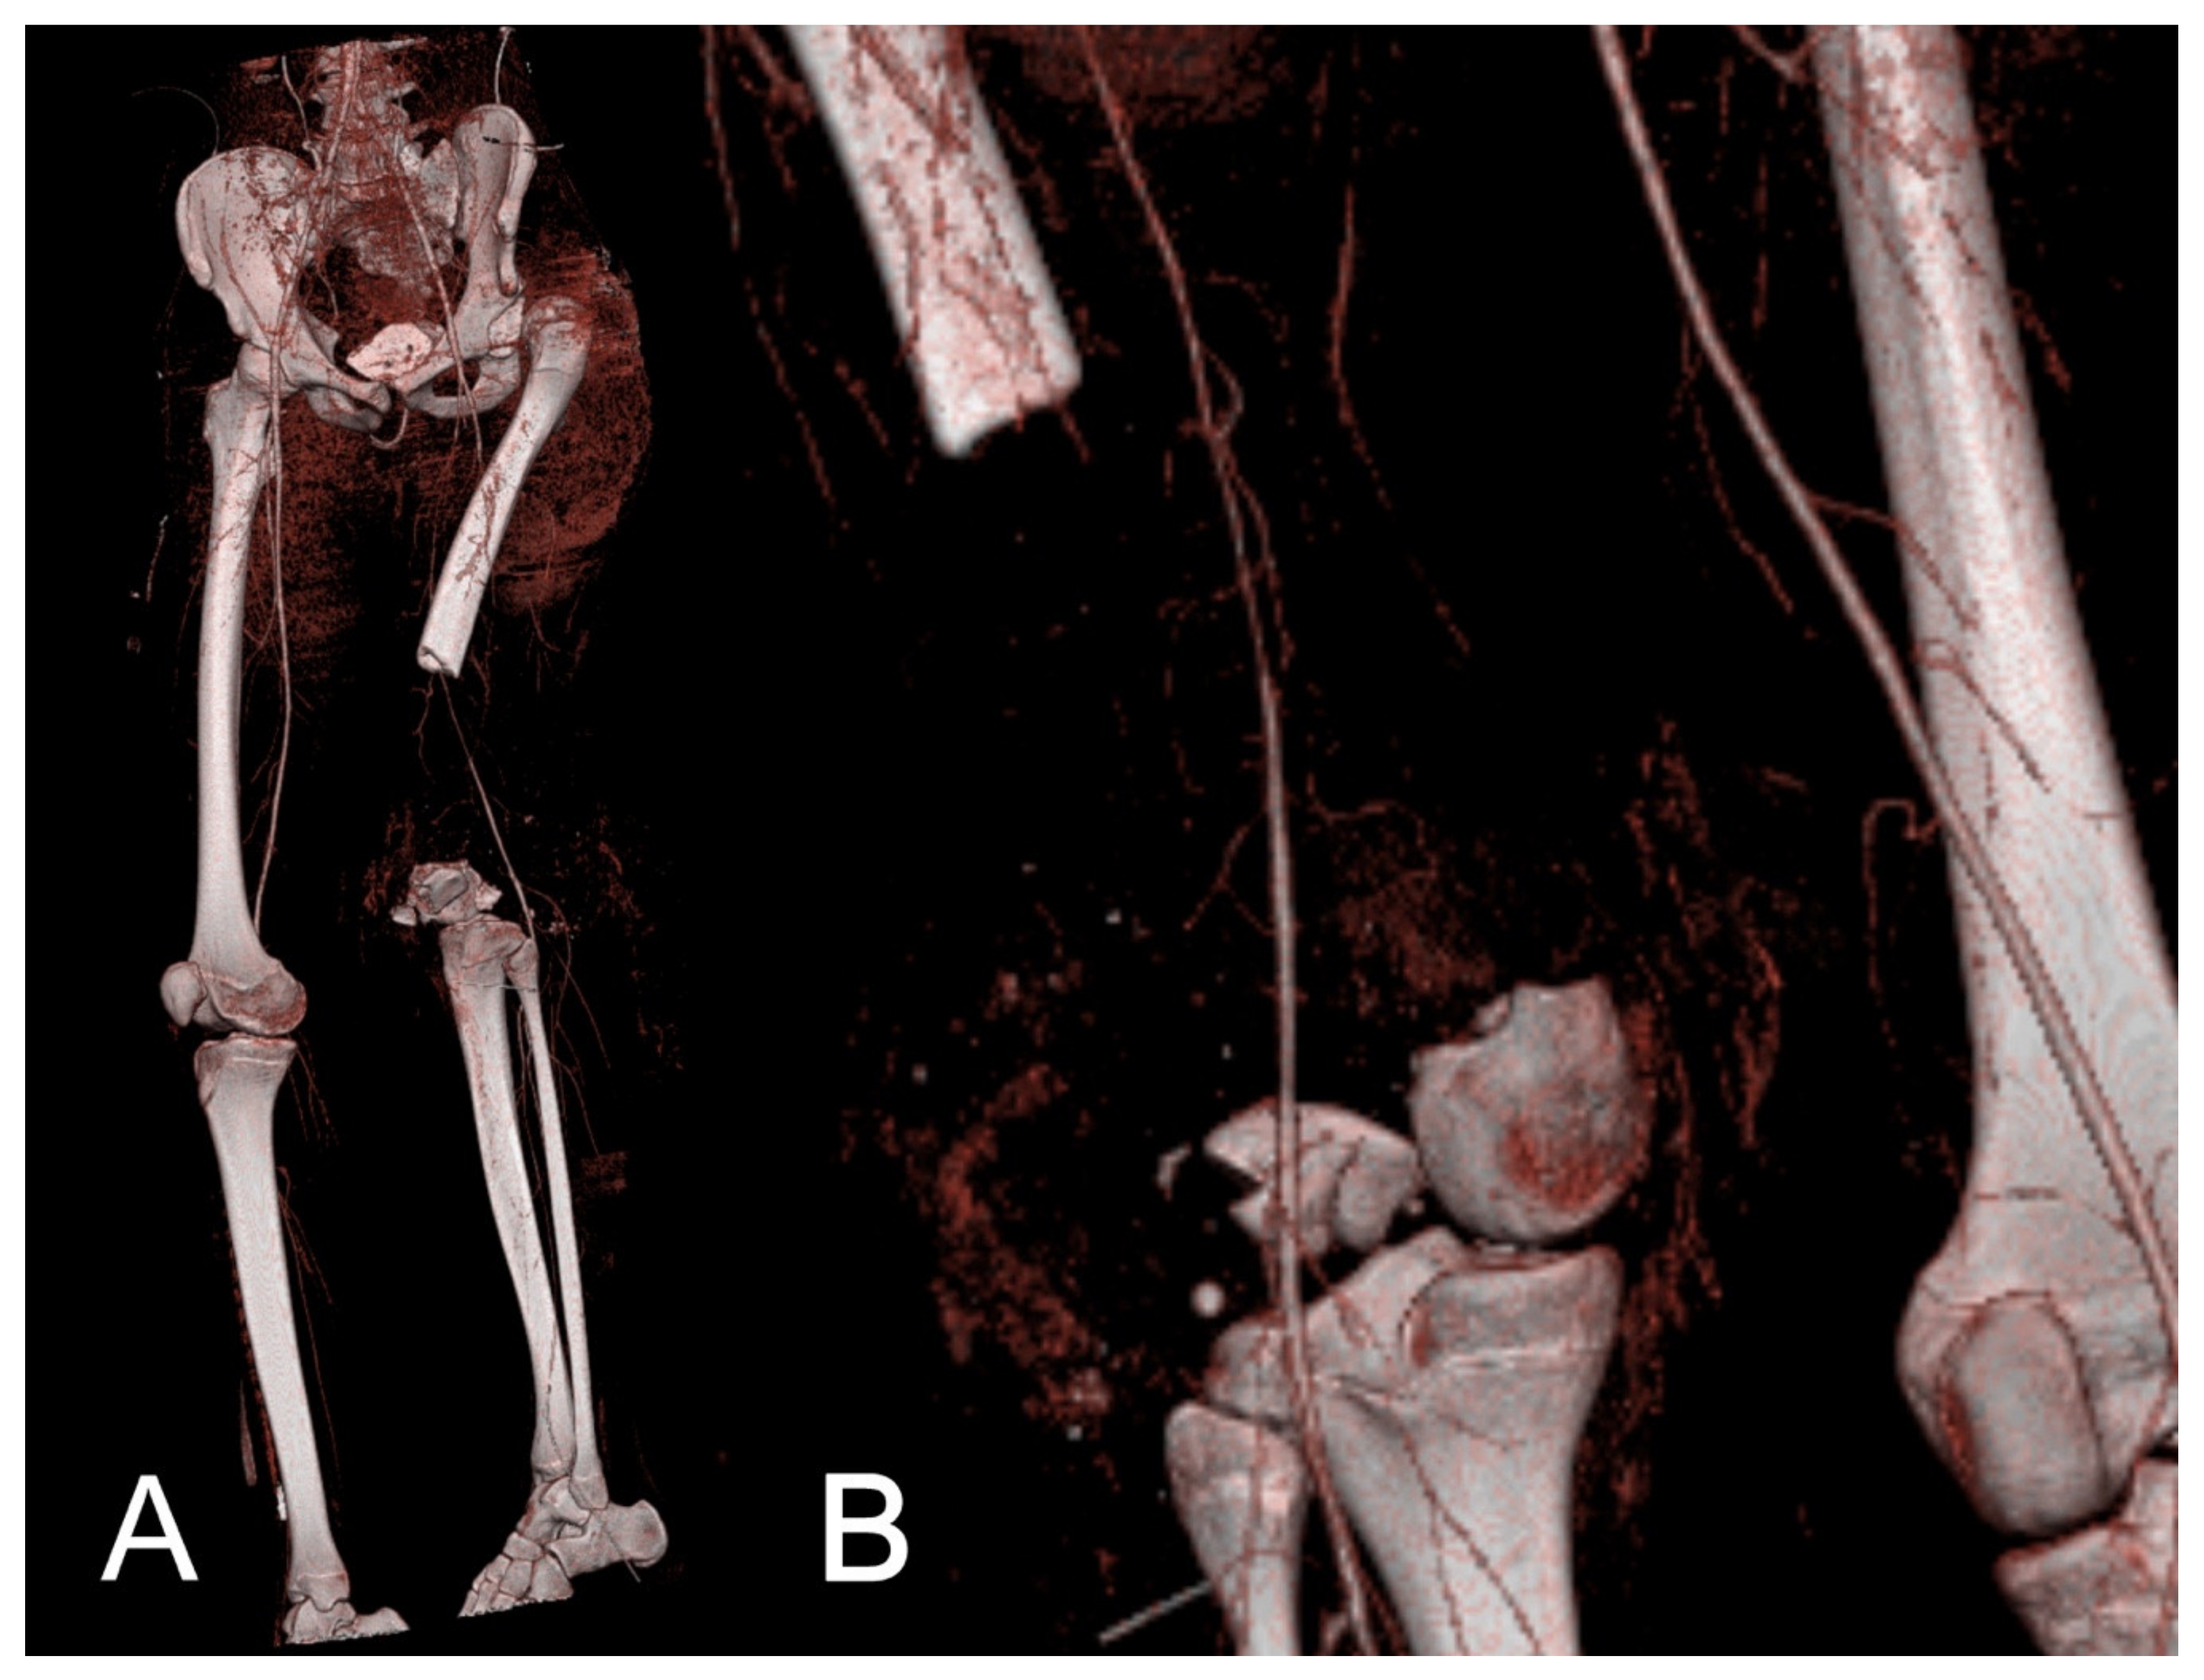

2.4.1. CT Angiography

| 3 | 70 | f | tib–fib | Fall | open Fx | PA, axial deviation, vessel lesion, TSF |